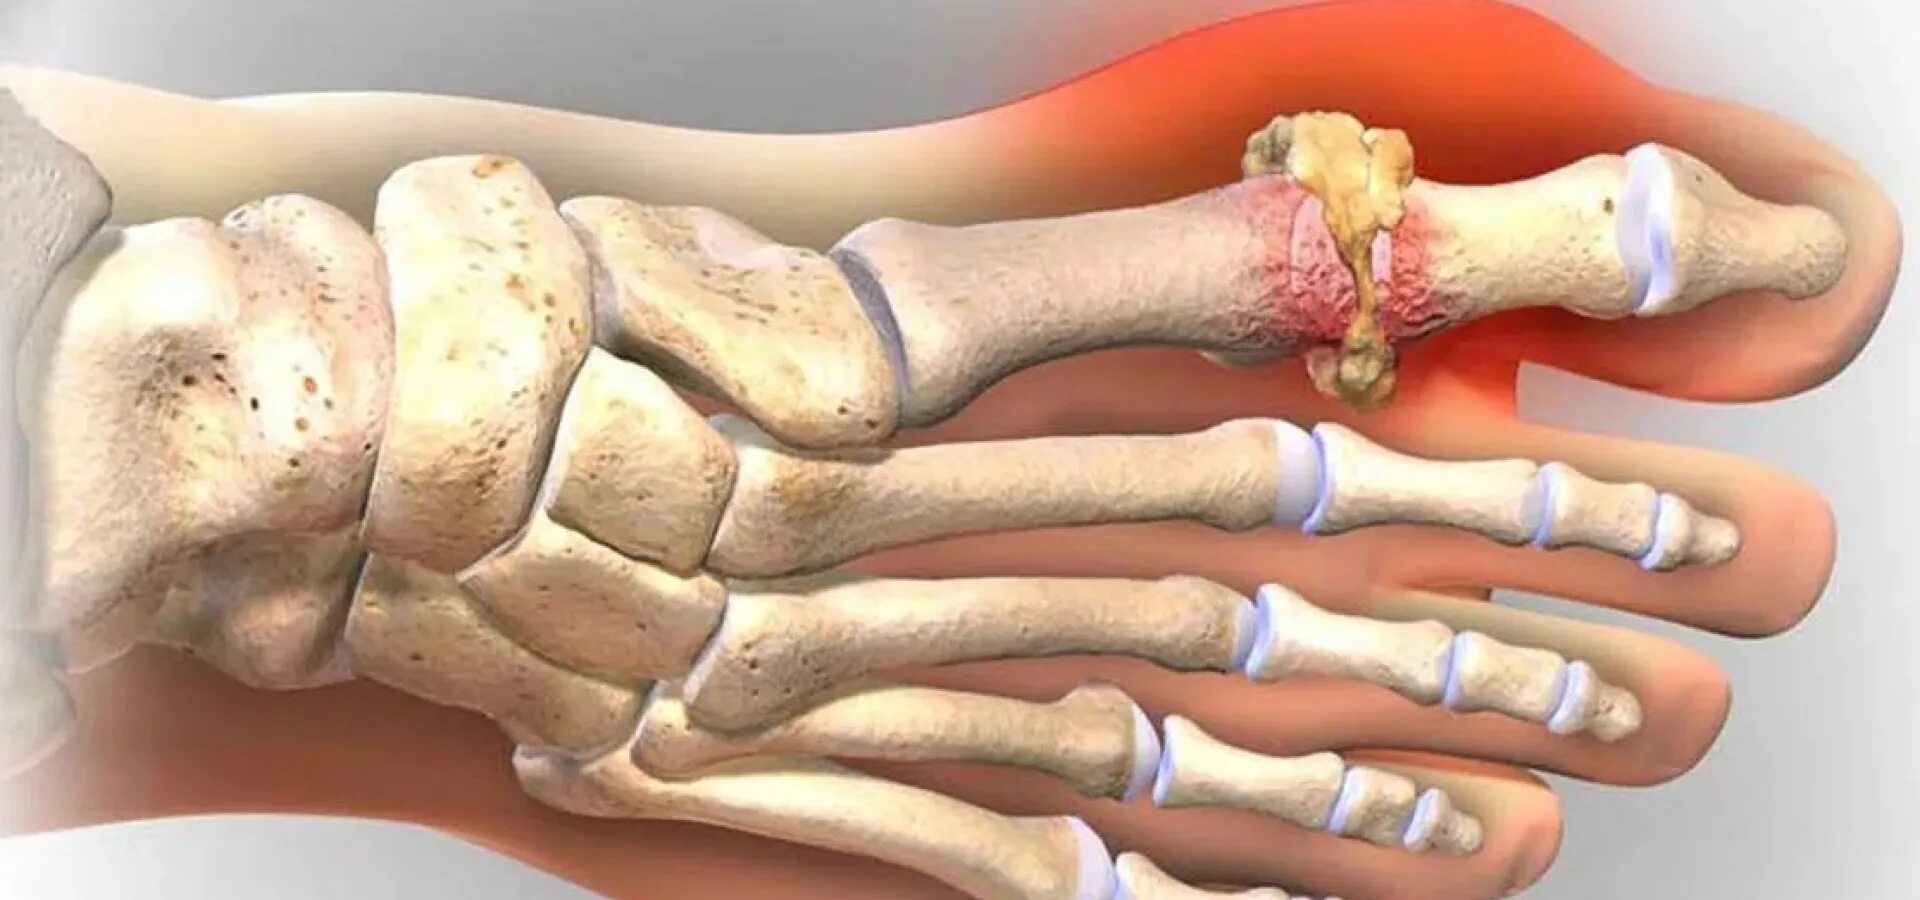

Подагра суставов стопы